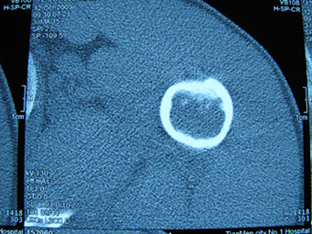

标题: X6404B:肱骨骨质破坏(CT片) [打印本页]

标题: X6404B:肱骨骨质破坏(CT片)

男,50岁,左肩部轻微疼痛,活动不便5个月就诊,近十天加重,无红肿热,间断理疗治疗无好转,既往5个月前左肩轻微拉伤史

骨巨?动脉瘤样骨囊肿?

内生软骨瘤。

内生软骨瘤。

内生软骨瘤?-----------

年纪大了,先要排除转移瘤。

髓腔内软组织肿块并斑片状钙化,考虑高分化软骨肉瘤可能性大。

考虑骨巨或动脉瘤样骨囊肿。

内生软骨瘤可能性大,期待结果。

孤立性骨囊肿。

内生软骨瘤可能性大

其内可见钙化,考虑软骨源性肿瘤,内生软骨瘤可能

但由于年龄较大,恶性软骨肉瘤待排

肱骨头内巨大软组织肿块并斑片状钙化,内生软骨瘤?骨巨细胞瘤?软骨粘液样纤维瘤?期待结果!

髓腔内软组织肿块并斑片状钙化,考虑高分化软骨肉瘤可能性大。

内生软骨瘤可能性大

肱骨头内巨大软组织肿块并斑片状钙化,内生软骨瘤?骨巨细胞瘤?软骨粘液样纤维瘤?期待结果

考虑内生软骨瘤?骨巨细胞瘤?

内生软骨瘤?骨巨细胞瘤?

先要排除转移瘤。